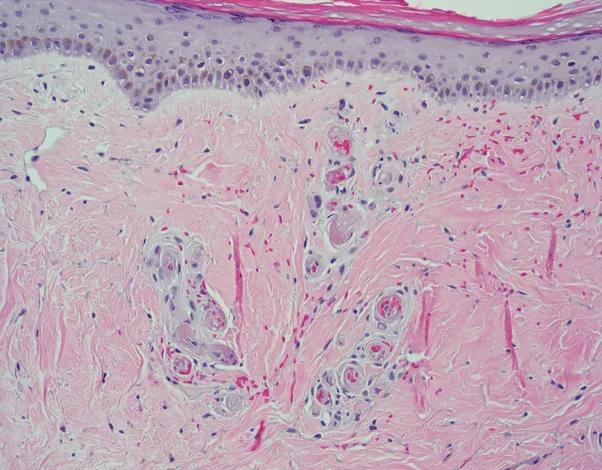

一名20岁的女性患者有8个月的疼痛性溃疡史,该溃疡会在双侧下肢缓慢愈合,形成白色疤痕。除此之外,她是健康的,并报告评分为4/10的疼痛局限于活动性溃疡,评分为8/10的下肢神经性疼痛,以及长期站立引起的水肿。检查显示在她的双侧踝和足背侧出现网状紫癜性斑块、结痂的紫色丘疹和与白色象牙斑块相关的浅表溃疡(图1)。穿孔活检支持青斑样血管病的诊断(图2)。未发现潜在的血栓形成倾向或自身免疫性结缔组织疾病。双侧下肢踝臂指数、静脉超声、多普勒、肌电图和神经传导研究正常。

穿孔活检显示乳头状和网状真皮血管壁内的纤维蛋白样物质以及管腔内的透明血栓。血管周围有轻度淋巴细胞浸润